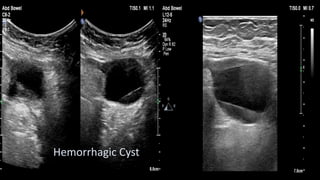

This document discusses the evaluation of right lower abdominal pain and lists appendicitis as a key cause. It notes that other potential causes include hemorrhagic cysts, heterotrophic pregnancy, salpingitis with pyosalpinx, funiculitis, and torsion of an undescended testis. The document was presented by Dr. A.S.M. Sufian of Cumilla Medical College Hospital and thanks the audience for their patience and listening.